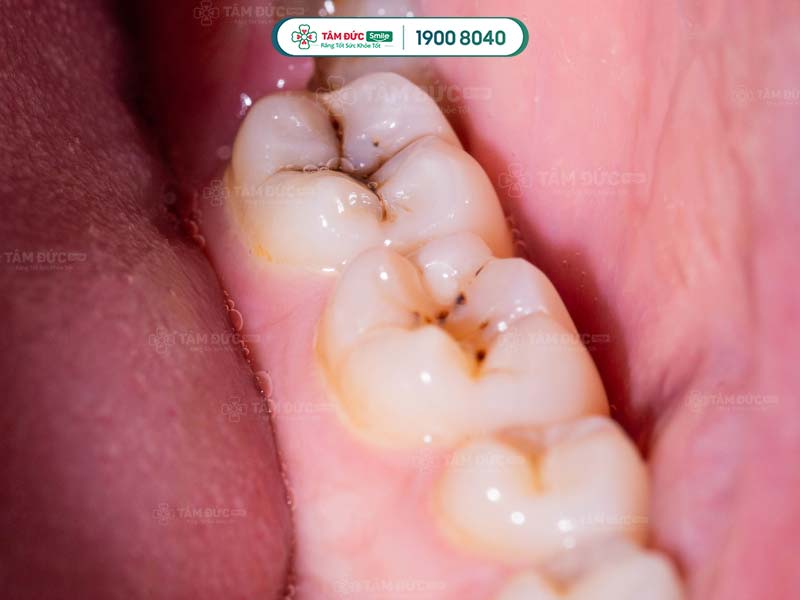

Sâu răng lâu dần làm răng bị suy yếu. Cấu trúc men răng và ngà răng bị phá hủy, xuất hiện những vết màu đen,...

Sâu răng gây đau nhức kéo dài tại vị trí sâu và các vùng lân cận. Nếu không điều trị kịp thời, tủy răng bị tổn thương quá mức, phải loại bỏ răng. Hôi miệng xảy ra khi hơi thở có mùi hôi khó chịu. Mùi hôi này xuất phát từ nguyên nhân bệnh lý hoặc vệ sinh răng miệng không đúng cách. Sâu răng hôi miệng không phụ thuộc vào độ tuổi, bất kỳ ai cũng bị sâu răng hay hôi miệng ít nhất một lần trong đời. Tuy không gây nguy hại lớn đến sức khỏe, nhưng lại ảnh hưởng nặng nề đến sự tự tin trong giao tiếp của người mắc phải.

Sâu răng là quá trình răng bị ăn mòn bởi axit được tiết ra từ vi khuẩn có hại trong khoang miệng. Mức độ sâu của răng tùy thuộc vào vị trí mà răng đã bị ăn mòn: men răng, ngà răng, tủy răng.